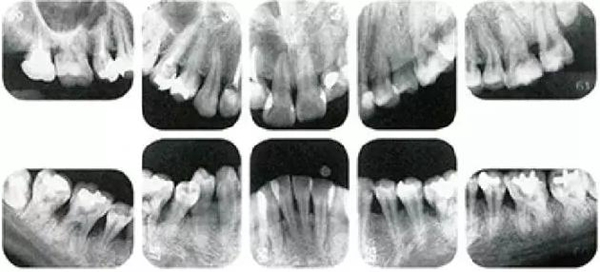

①的患者是35歲女性。4~10mm的牙周袋和大量的牙石。特別是在左上、右下、左下的磨牙處能看到大量牙槽骨吸收。這名患者是慢性牙周炎,僅在磨牙處有局部由風(fēng)險(xiǎn)因子導(dǎo)致(解剖學(xué)形態(tài))導(dǎo)致的重度病癥發(fā)展。

另一方面25歲女性的參考病例

②將會(huì)是什么樣的呢?左上、右下、左下的磨牙處有大量牙槽骨吸收,考慮到其發(fā)病年齡,斷定為是侵襲性牙周炎局部型。

但是實(shí)際上參考病例①和②是同名患者,①是②10年后的狀態(tài)。這名患者間隔10年后來(lái)就診,讓我們可以確認(rèn)到癥狀的變化。

●參考病例① 35歲女性

35歲女性。妊娠4個(gè)月。過(guò)去雖然接受過(guò)刷牙指導(dǎo),但菌斑控制狀態(tài)依然不理想?;颊哂邪l(fā)現(xiàn)自己刷牙時(shí)牙齦出血。

●參考病例② 25歲女性

25歲女性。菌斑控制狀態(tài)不好。齦溝除磨牙處外全在3mm以下,X光照片上左上、右下、左下的第一磨牙上有垂直性骨吸收。這個(gè)病例是參考病例①10年前的狀態(tài),是典型的侵襲性牙周炎局部型。